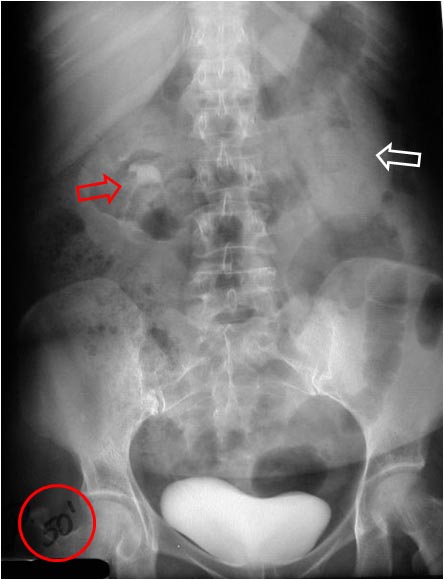

SIGNO VESICAL

Signo visible en la radiografía simple de abdomen que permite diferenciar entre una vejiga muy distendida (globo vesical) y una masa pélvica de otro origen. La distensión de la vejiga se ve como una densidad homogénea redondeada u oval de borde superior definido, que ocupa la pelvis obliterando las zonas laterales de la pelvis y desplazando lateralmente el ciego y el sigma.

Las flechas negras marcan el borde superior vesical bien definido. Obsérvese el borramiento de planos grasos en la pelvis (flecha naranja), el desplazamiento lateral del ciego (flecha blanca) y superior del sigma (flecha roja).